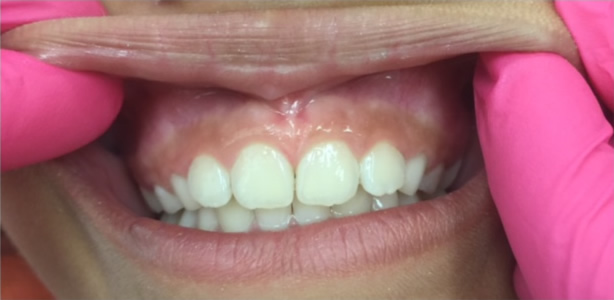

A lip-tie occurs when the upper lip remains attached to the upper gum. Challenges that can occur in children and infants with moderate to severe lip-ties include:

• Formation of a large gap between the maxillary central incisors, called a diastema

• Repeated trauma to the maxillary frenum because it is so low and prominent